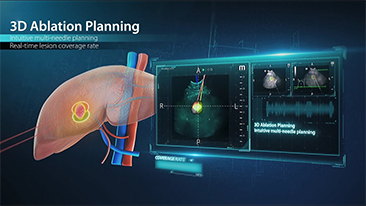

How Clearly Can You See a Liver?

Ultrasound contrast imaging plays a significant role in identifying focal liver lesions, such as hemangioma or liver cancer.

Ultra-wide non-linear UWN+ contrast imaging technology provides better penetration, higher contrast-tissue ratio, with lower MI and longer perfusion time observation.